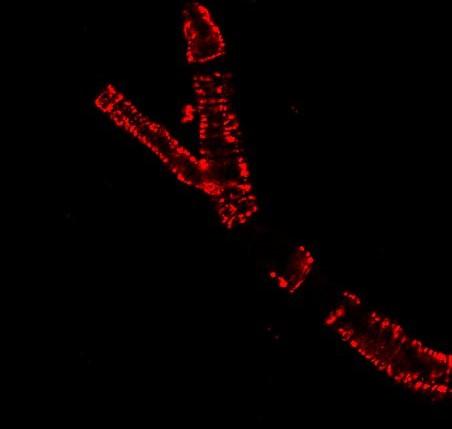

image: This image shows an isolated cerebral arteriole from a mouse model, marked by a live-cell dye.

Osama Harraz, Ph.D., University of Vermont Larner College of Medicine

Larner College of Medicine at the University of Vermont